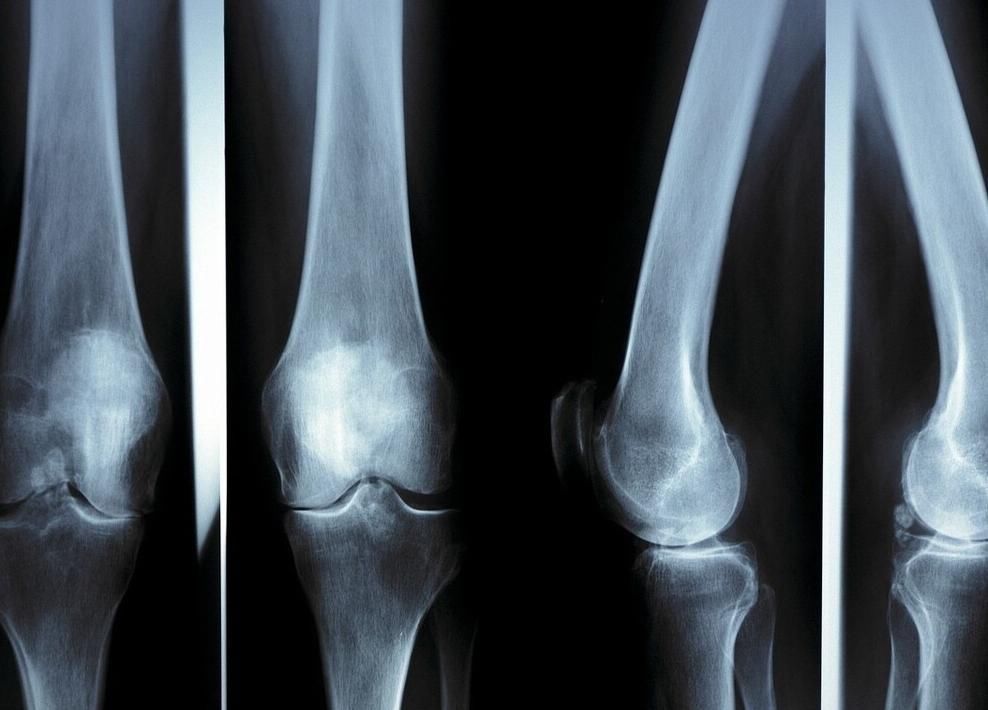

身高的变化主要是人体骨骼的生长,儿童平均每年在3厘米左右,在青春期到来之前个头会有一个迅速的提升,一年甚至长6-8厘米。在长高的过程中骨龄是孩子发育的指标,如果年龄大于他骨龄孩子就会生长迟缓,如果年龄小于骨龄就会早熟。